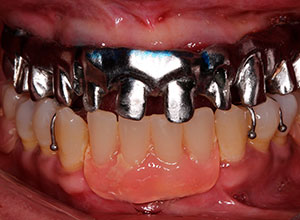

Por otro lado, este tipo de rehabilitación también está indicada en aquellas personas que, aunque aún mantienen dientes en la boca, dichas piezas dentales presentan un pronóstico imposible a corto plazo y están abocados al edentulismo total.

El día de la cirugía la paciente sale de la clínica con prótesis inmediatas removibles las cuales fueron elaboradas con modelos de trabajo tomados previo a la cirugía.

La prótesis dental híbrida es una estructura fija atornillada sobre implantes dentales que tiene como objetivo reponer las piezas dentales y tejidos blandos -encía- perdidos.

Dicha sensación se debe fundamentalmente a que es fija y no lleva paladar. Por ello, aporta gran estética, seguridad y comodidad a quien la lleva.

La prótesis dental híbrida consta de una estructura de metal recubierta de varias capas de porcelana blanca y rosa que dan la estética de los dientes y de la encía.

Dicha estructura se atornilla sobre los implantes que se han colocado previamente en el hueso mediante la cirugía.